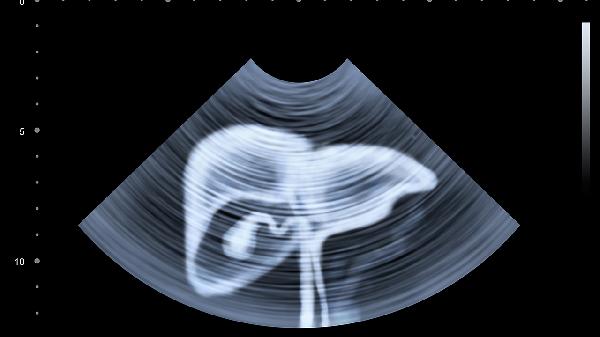

早上空腹飲酒、濫用藥物、長期不吃早餐、過量飲用咖啡以及憋尿等習慣特別容易傷害肝臟。肝臟作為人體重要的代謝器官,這些行為可能干擾其正常功能,增加肝臟負擔,甚至誘發(fā)脂肪肝、肝炎等疾病。